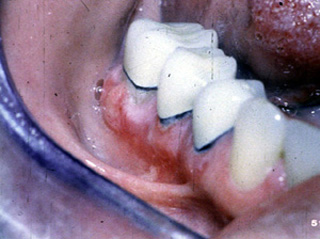

Este paciente también estaba recibiendo un diurético. En este caso la reacción liquenoide  tiene una apariencia muy diferente. Los encía se encuentra muy eritematosa y dolorosa; la ulceración es evidente en la encía marginal. Tras interrumpir el diurético la condición se resolvió.